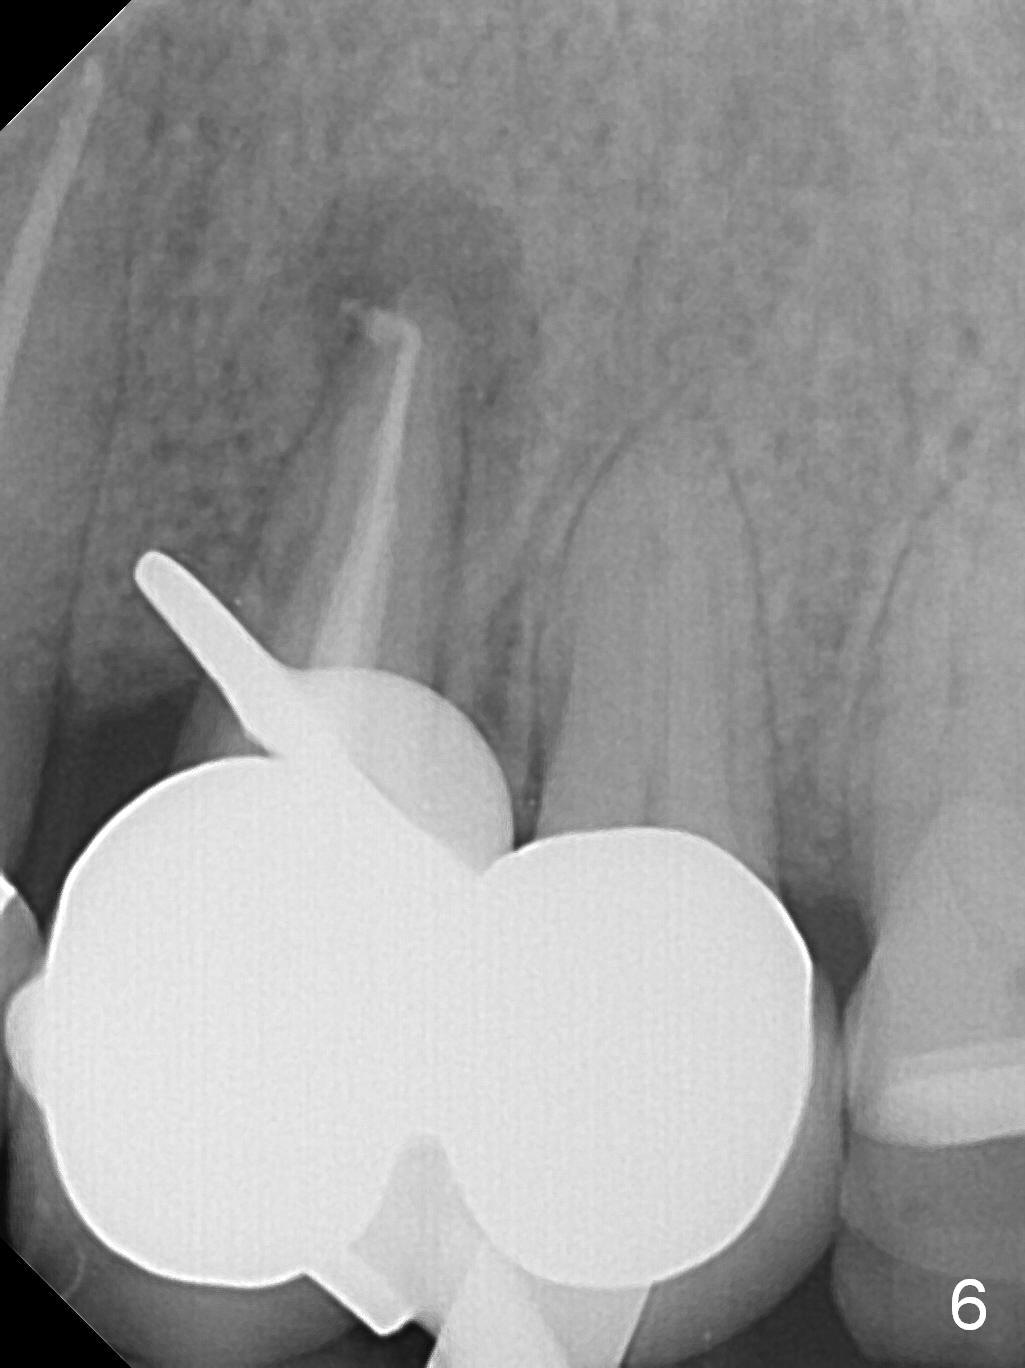

A 43-year-old woman has a persistent, asymptomatic fistula buccal to the tooth #12 (Fig.1,2). Prior to treatment, a #30 gutta percha is inserted into the fistula to confirm diagnosis (Fig.3). Hand files #15 and 20 are inserted to the buccal and lingual canals at 18 mm, respectively (Fig.4). Master cones (30/.04) are inserted buccally and lingually for 18 and 17 mm, respectively (Fig.5). There is minimal paste leakage after finishing RCT (Fig.6). Out of curiosity, the fistula is immediately curetted with removal of 2 small pieces of apparently leaked paste with minimal discomfort (total anesthetic: Xylocaine 34 mg, Epi 17 mcg). The fistula is expected to heal in 2 weeks.